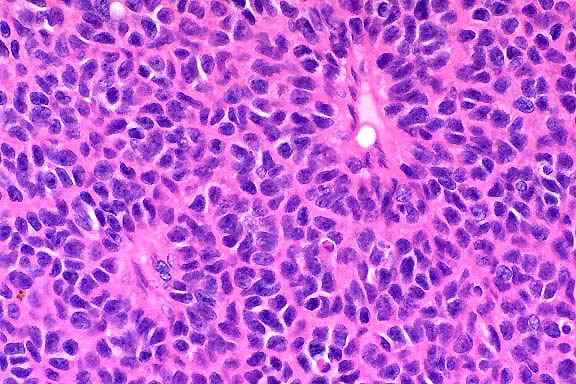

40x

obj

- Case 12-4. Kidney. The cytoplasm of many proximal

tubules is rarified, somewhat foamy, and often contains globular

to to polygon shaped eosinophilic inclusions.

- Transmission Electron Micrograph, 1540X. Kidney, proximal

tubules. The electron micrograph illustrates portions of four

proximal tubules lined by tall cuboidal epithelial cells with

a brush border, oval nuclei with dispersed chromatin and 1-2

small nucleoli, and abundant mitochondria, many arrayed perpendicularly

to the basement membrane. The epithelial cells are swollen, vacuolated,

and have numerous, intracytoplasmic osmiophilic amorphous deposits

(secondary lysosomal contents) surrounded by an electron-lucent

space and a single membrane (fused lysosomes) and large, rectangular,

rhomboid or irregular to needle-like crystalline intralysosomal

deposits (alpha 2m globulin). Interspersed between the proximal

tubules (lower left) are small spindle cells with oval nuclei

(mesangial cells).

- Conference participants generally agreed with the following

description of the submitted electron micrograph:

- Kidney, proximal convoluted tubule: There are portions

of at least three tubular structures, each lined by contiguous

cuboidal to rectangular cells aligned along a prominent basement

membrane. Along the luminal border of these cells are lush microvilli.

The cells have irregularly oval nuclei which contain abundant

euchromatin and peripherally clumped heterochromatin. One nucleus

has two small nucleoli. The cytoplasm contains abundant, closely

packed, elongate mitochondria that are often arranged perpendicularly

to the basement membrane. There is a moderate amount of rough

endoplasmic reticulum within the cytosol. Multifocally near the

cell apices there are few pinocytotic vesicles. Interposed between

adjacent tubular basement membranes are a few small cells with

scant cytoplasm and oval to angular nuclei (fibroblasts or other

interstitial cells).

- Multifocally within the cytoplasm of the tubular epithelial

cells there is an accumulation of numerous irregularly shaped,

variably-sized, electron-lucent vacuoles that often coalesce

(enlarged lysosomes). Superimposed within these vacuolated areas

are numerous smaller, intensely electron-dense, variably-sized

granules. Within most tubular epithelial cells in the vacuolated

areas there are few electron-dense crystals that vary from thin

spicules with sharply pointed ends, to large hexagonal or rhomboidal

crystalline structures. The enlarged lysosomes containing the

previously described material displace mitochondria and nuclei

peripherally.

- Case 12-4. Electron micrographs

- Many of the tubular epithelial cells in the central tubule

at the center of the photo are swollen and expanded more laterally

than apically due to the vacuolated inclusions. Residual cellular

organelles are peripheralized and compartmentalized. The compartmentalized

mitochondria have lost proper orientation and are no longer aligned

perpendicular to the basement membrane. In the epithelial cell

in the center of the photo, the lateral cell boundaries are markedly

widened, and the nucleus is compressed and flattened against

the cell base (see cell labeled "4" at AFIP website).

Because these ultrastructural changes probably alter normal cellular

function, the morphologic diagnosis of "cellular degeneration"

is appropriate.